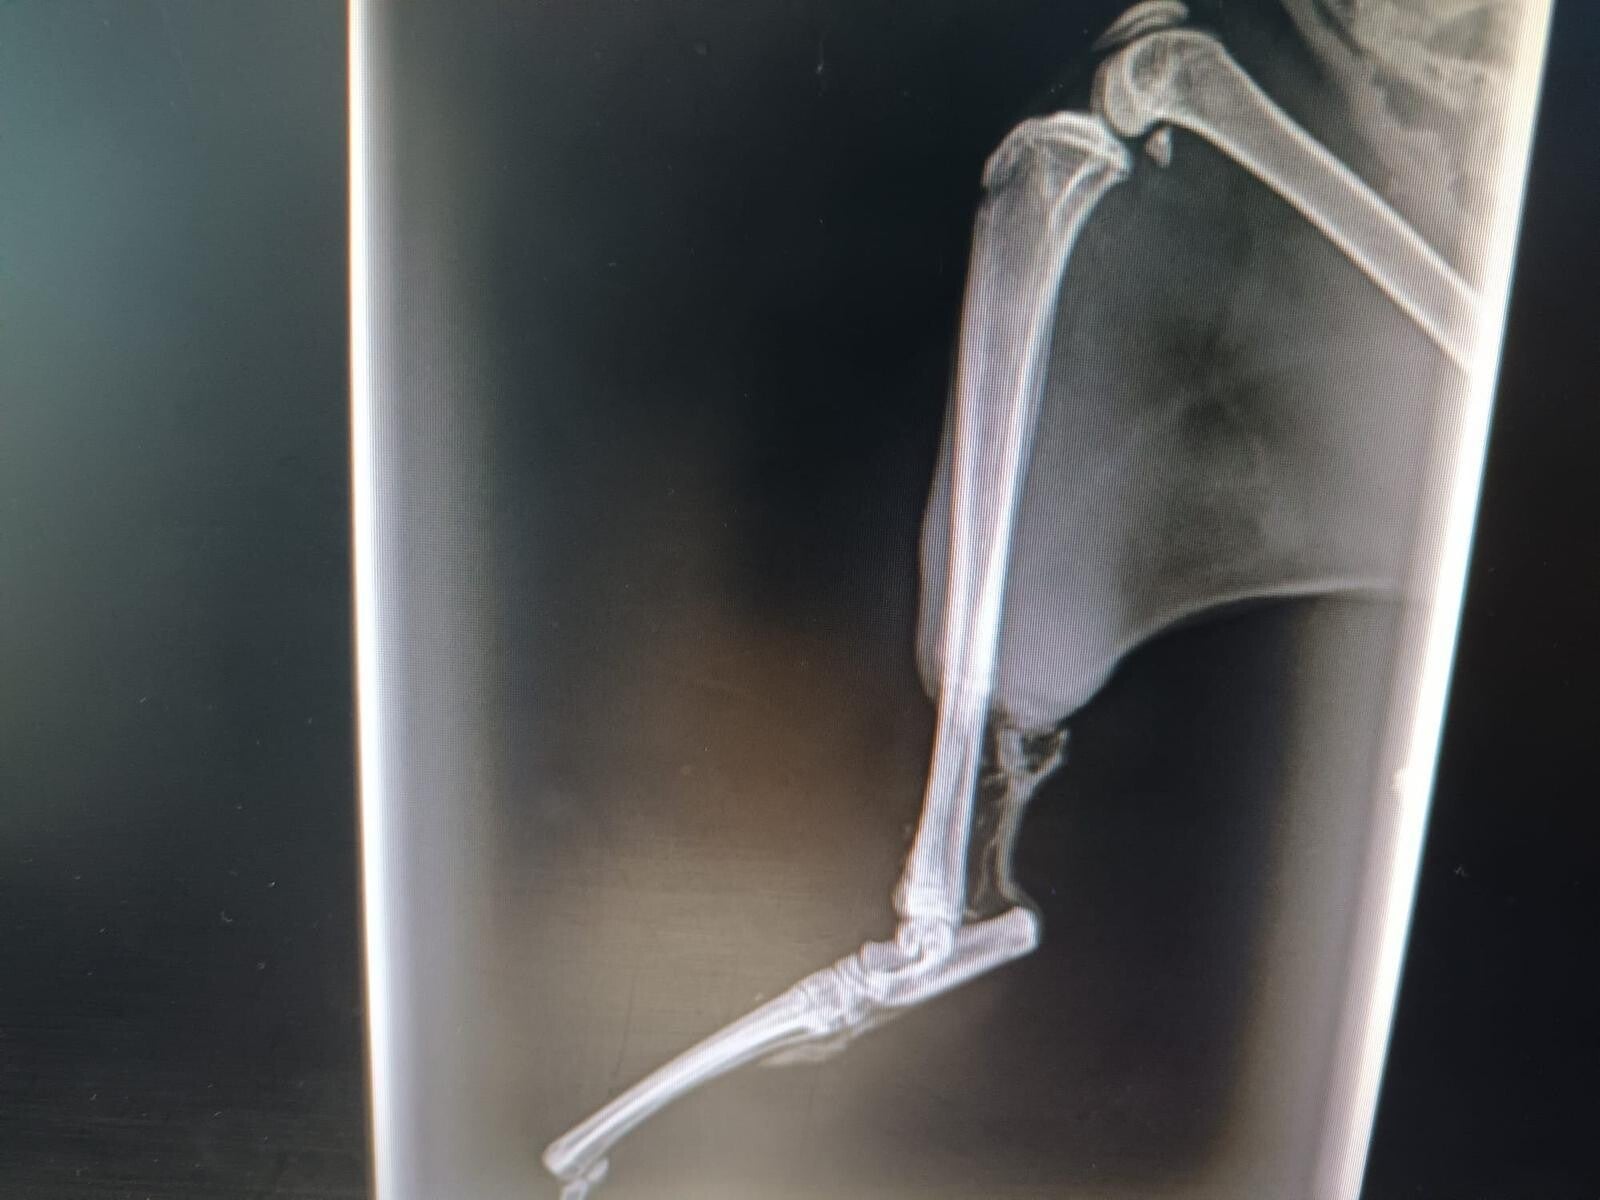

LISA - Ze verscheen in een dorp met haar benen volledig vernield en verrot (sorry voor de foto's, want ze zijn hard).

Ze werd gered door BICHOSRAROS.ORG en haar twee achterpoten werden geamputeerd. Tegenwoordig beweegt en klimt ze, ondanks dat ze maar twee voorpoten heeft, als een behendige acrobaat over de krabpalen!